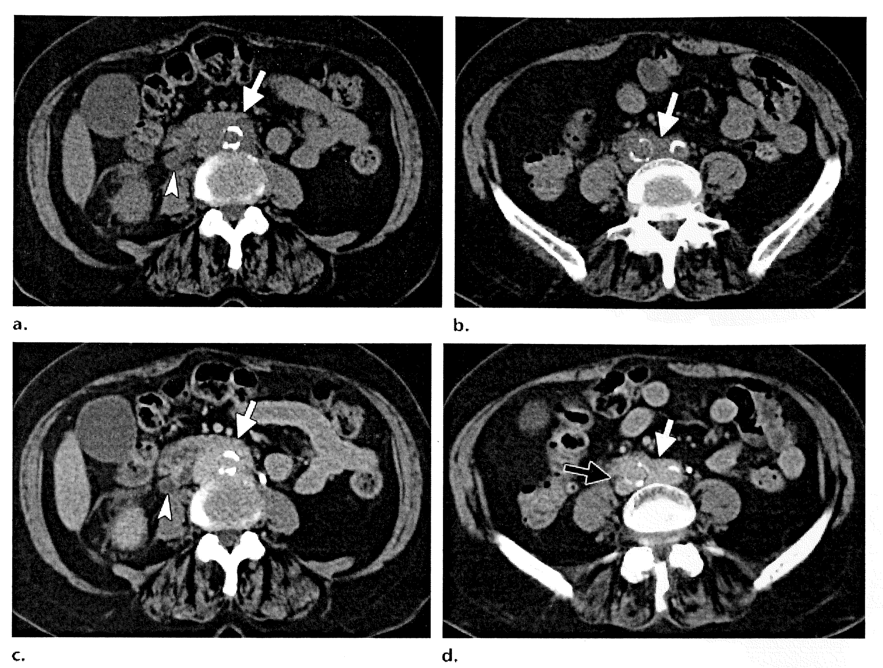

2015年段階で後腹膜線維症のCT所見の典型的所見を記載したのはCalafa RQ等7) 論文で、図2 a b c d の説明が丁寧です。

図2 a b c d (Calafa RQ等7) から引用)

図2 abcd